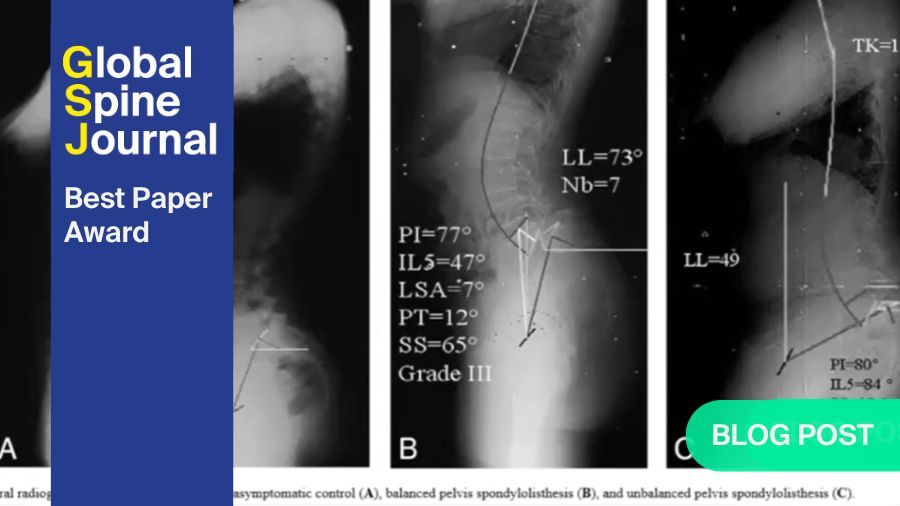

Spondylolisthesis, the forward translation of the vertebra body over its caudal counterpart, is more prevalent in patients above 50 years old, and is likely reflective of degenerative aetiology and exhausted physiological reserves with acute worsening of the condition. This is supported by the concomitant findings of sagittal compensation such as increased PT, KAA and SCA in patients with spondylolisthesis (Figure 1).

Additionally, higher PT and SS, alongside changes in LL and SCA were evident in association with spondylolisthesis. While PT can fluctuate with postural changes and is influenced by spinopelvic compensation mechanisms, the simultaneous increase in SS, which conventionally acts reciprocally with PT, reinforces that this increase is likely to be also contributed by pelvic morphology. This can be further explained by the equation PI = PT + SS, where patients with a large PI naturally bears a larger PT and SS. This hypothesis is further supported in the observation of larger L5I, L5T and L5S associated with L4/5 spondylolisthesis. The absence of similar findings in other intervertebral levels is likely due to the low prevalence of spondylolisthesis at those levels.